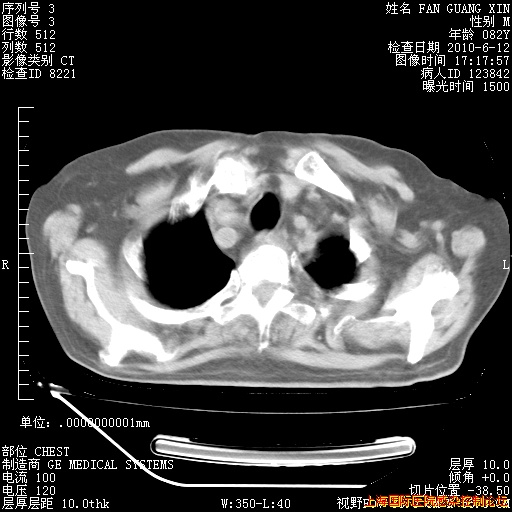

补发6月12日肺部CT肺窗

6月12日肺窗